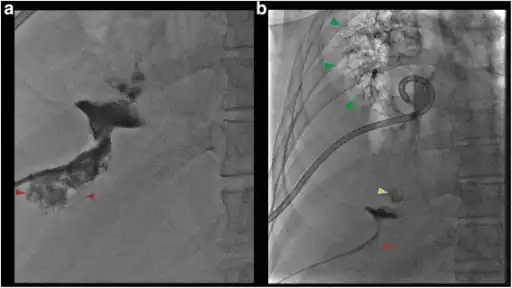

a) Fluoroscopic view shows contrast in collapsed liver abscess red arrow b) fluoroscopic view shows contrast tracking from the liver abscess red arrow